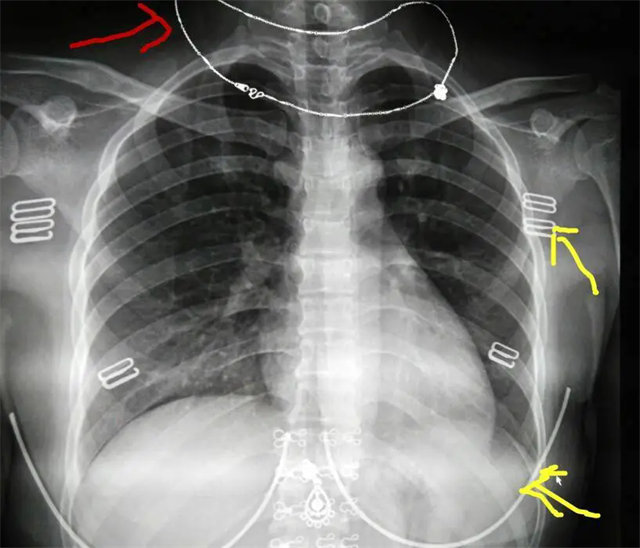

缺陷:兩肩胛骨未拉開肺野之外,吸氣不完全,且存在金屬飾品遮擋。

解決:去除金屬飾品及內(nèi)衣后重新按標準體位攝片即可。